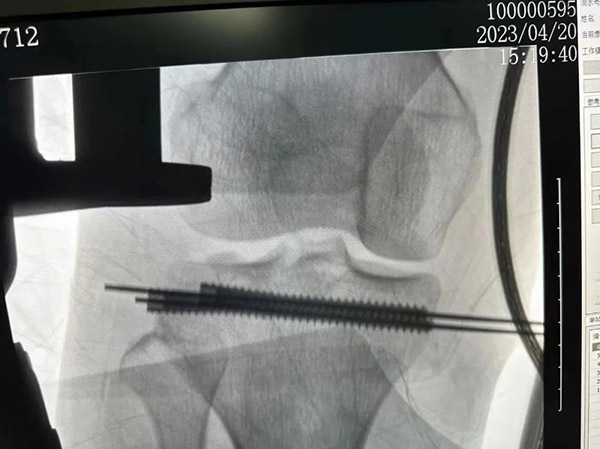

康復(fù)科近期收治了一位脛骨平臺(tái)骨折內(nèi)固定術(shù)后的患者,該患者術(shù)后自己在家自行康復(fù)訓(xùn)練兩個(gè)月,未能實(shí)現(xiàn)應(yīng)有的關(guān)節(jié)活動(dòng)度,不能正常行走,仍需拄雙拐才能夠進(jìn)行簡單的步行,在骨科復(fù)查后建議到康復(fù)科就診。